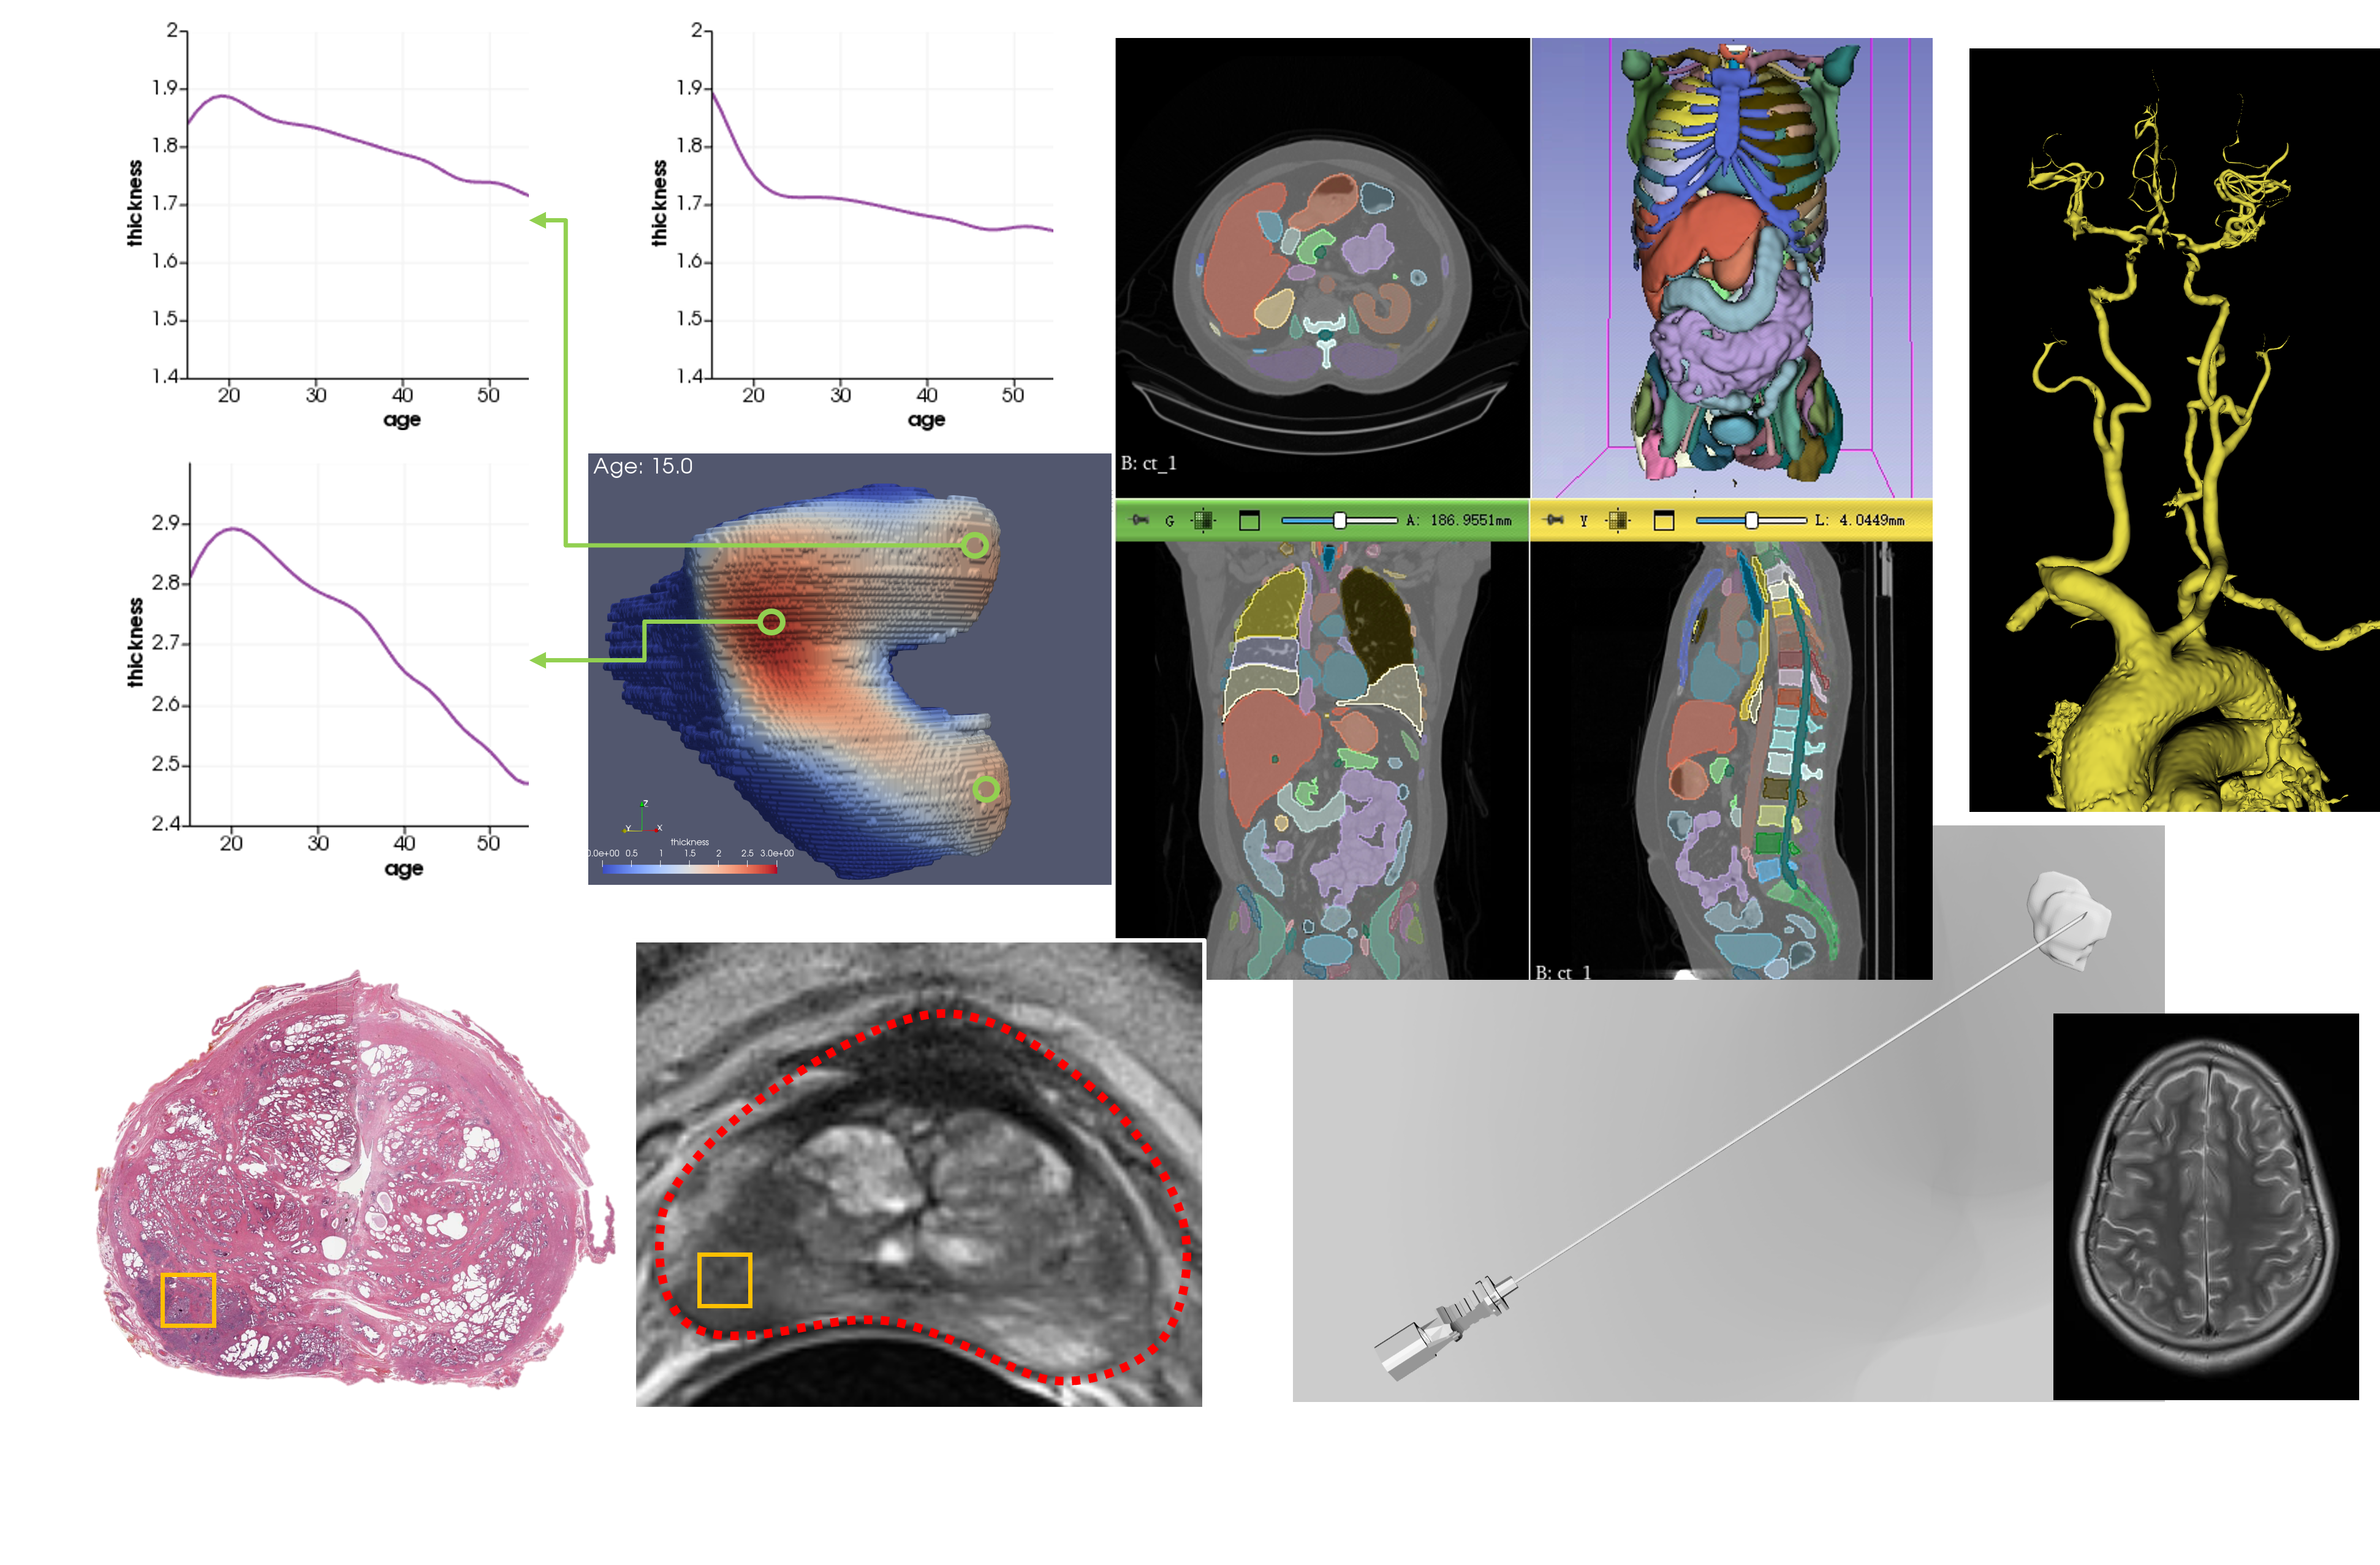

• L Si*, K Xuan*, et, al. “Knee Cartilage Thickness Differs Alongside Ages: A 3-T Magnetic Resonance Research Upon 2,481 Subjects via Deep Learning,” Frontiers in Medicine, vol. 7, p. 1157, 2021. (*Equal Contribution, IF=5.09)

方向一:医学影像处理

我们专注于医学影像分析作为主要研究方向,利用先进的计算机视觉和深度学习技术处理并解析复杂的医疗图像数据。目标是通过精准的图像分割、特征提取、图像合成技术,以及病变检测与分类方法,辅助医生做出更准确的诊断决策,促进个性化治疗方案的发展,提高早期疾病发现概率与患者治疗效果。

磁共振图像大数据分析

计算机辅助诊断

快速磁共振成像